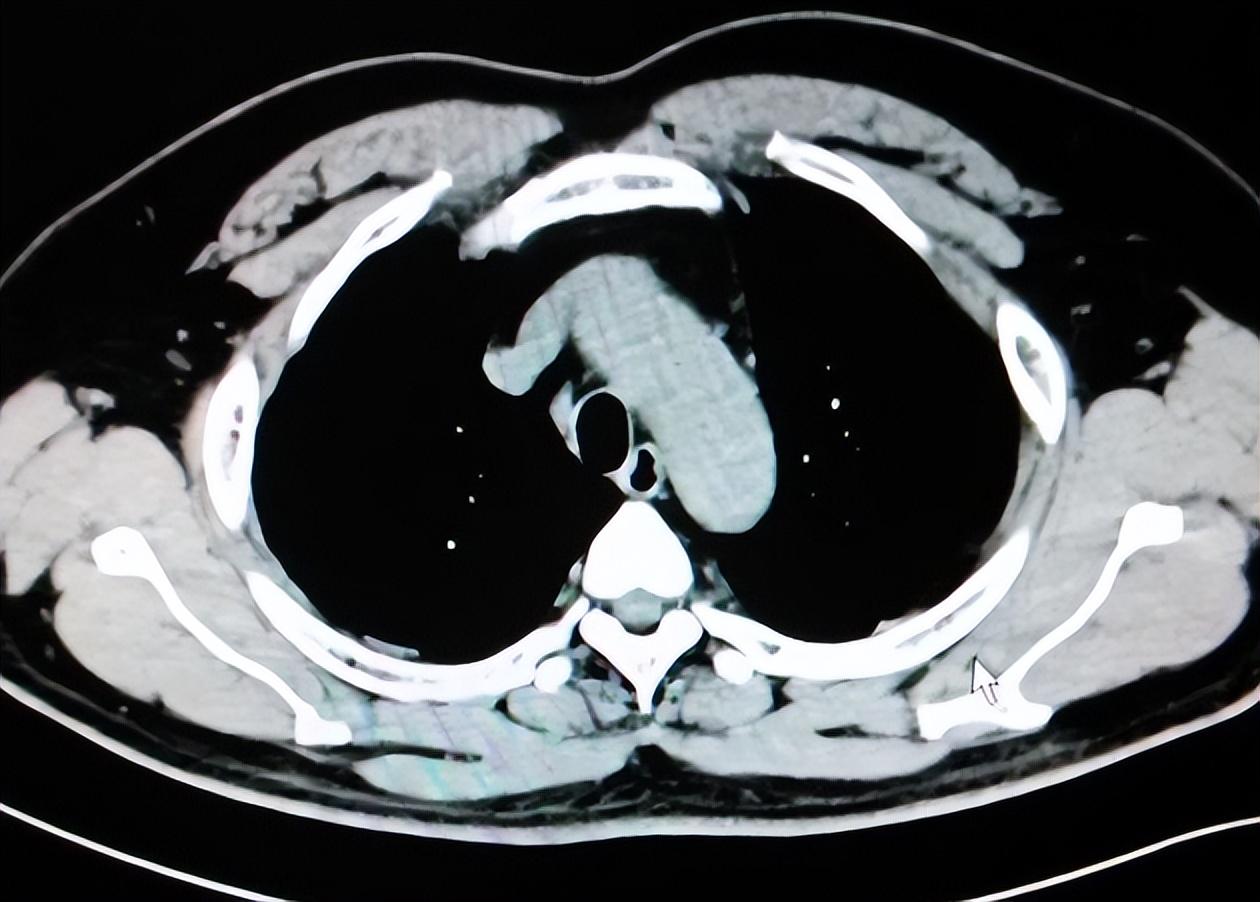

提醒:身体这4个部位疼痛,可能是肺癌早期的信号 高师傅六十出头,退休后生活很规律,早睡早起、饭后遛弯,平时也不怎么生病。半年前开始总觉得右肩不舒服,像落枕一样疼,贴膏药没啥用,按摩也缓解不了。 慢慢地连右背也开始酸,有时还放射到手臂。他以为是颈椎毛病,就跑去做了颈椎核磁,结果一切正常。后来体检时做了低剂量肺部筛查,才发现右上肺有一个可疑结节,进一步检查被确诊为肺癌早期。 不少人都以为肺癌只有咳嗽、咳血这些典型症状,其实有些早期患者根本不咳,反而先是身体其他地方的疼痛引起注意。 尤其是四个部位,如果莫名开始疼,而且持续不好,真的不能只当小毛病看,可能就是肺部病变在发信号。 肩膀是其中一个。肺尖的肿瘤容易刺激到臂丛神经,表现出来就是肩背部钝痛,特别是一侧持续痛,还总是在夜里加重,用止痛贴和热敷效果都不明显。 还有胸骨后和肋骨间的闷痛,也值得注意。有的人描述不清楚,就是觉得胸前总是堵,压着不舒服,尤其吃饱饭或深呼吸时更明显。这可能是肺部肿块逐渐增大,压迫到了胸膜或胸壁,才会反映到表面的疼痛感。 第三个常见部位是上腹部。有的人查了胃肠没毛病,却老觉得胃胀、上腹痛,怎么调也不好。其实右肺下叶病变或者胸膜受累,也能牵扯到横膈神经,进而让人误以为是胃出了问题。这类疼痛不一定剧烈,但总是阴沉沉地跟着人走。 最后是颈部。有些肺癌患者在早期会出现锁骨上淋巴结肿大,颈部也会有隐痛,甚至按上去有点硬块。这种情况特别容易被忽视,觉得是落枕或者脖子没睡好,但其实是肺部病灶开始向周围扩散的信号。 一项涉及三万多人的肺癌筛查数据显示,有接近一成的早期肺癌患者,最早的就诊原因并不是呼吸道问题,而是肩背、胸部或颈部疼痛。 现在低剂量肺部CT已经越来越普及,费用也不高,如果年纪超过四十五岁,又有长期吸烟、家族史或者出现这些不明原因疼痛的人群,真的该主动去筛查一下。不是等咳嗽、咳血来了才重视,那时候大概率已经不是早期。 高师傅现在已经做了微创手术,恢复得不错。他说最开始真没想到肩膀疼能跟肺扯上关系。这个误区很多人都有,痛了就以为是肌肉、骨头问题,结果差点耽误了最关键的治疗窗口。 疼痛这件事不能光靠扛,也别一味自己判断。特别是那些说不上来为啥疼、也说不清是哪里疼的状态,一定要多长点心。 身体的语言很诚实,它不会无缘无故地给你制造麻烦。听懂了,病就不容易拖太久。早点发现,才是对自己最大的负责。